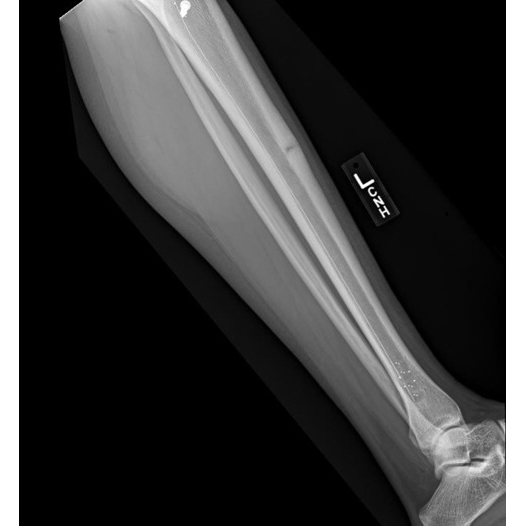

Osteoid Osteoma with associated overlying Anterior Tibial Stress Fracture

She was initially treated conservatively with walking boot and non-steroidal anti-inflammatories and held from sport participation. Due to lack of improvement, her scan was repeated and showed an osteoid osteoma with an overlying anterior tibial stress fracture. She then had the osteoma ablated and a carbon fiber rod placed for the stress fracture in order to limit image artifact if there needs to be reevaluation of the osteoma site. Case Photo #8

Anterior tibial stress fractures are rare but occur in athletes. Due to their location, tensile forces, and blood supply, they usually require surgery. Osteoid Osteomas are benign tumors commonly found in the tibia. They are usually self-limited but can ablated. Both present similarly and are on the differential for anterior leg pain. This highlights a patient that had an osteoid osteoma with an overlying anterior tibial stress fracture in the same location and required treatment for both. Not only is it unique that both pathologies were present, but also, a carbon fiber rod was used instead of the usual IM rod to not distort future MRI images in case they are needed for tumor recurrence.

Bone stress injuries of the tibia exist on a spectrum ranging from tibial stress syndrome to higher-grade stress reactions and stress fractures. MRI is the gold standard for staging. Tibial stress syndrome is characterized by periosteal edema only, while progression may lead to a stress reaction with bone marrow edema. A stress fracture is defined by cortical involvement and the presence of a visible fracture line.

Anterior tibial stress fractures are considered high-risk and, as noted by the authors, often require surgical management, particularly when the dreaded black line is seen on plain radiographs. In contrast, the more common medial tibial stress fracture is typically managed non-surgically.